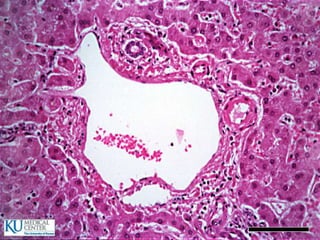

Glándulas salivales principales

 Glándula parótida

 Glándula submaxila

 Glándula sublingual

Saliva

 Alcanza un volumen de 1000 ml en 24h

 Funciones:

 Humedece de forma constante la cavidad bucal

 Ayuda a limpiar restos alimenticios

 Humedece los alimentos

 Mantiene el equilibrio hídrico

 Composición:

 Amilasa y maltasa

 Lisosima y Rnasa Dnasa

 Gammaglobulinas: IgA